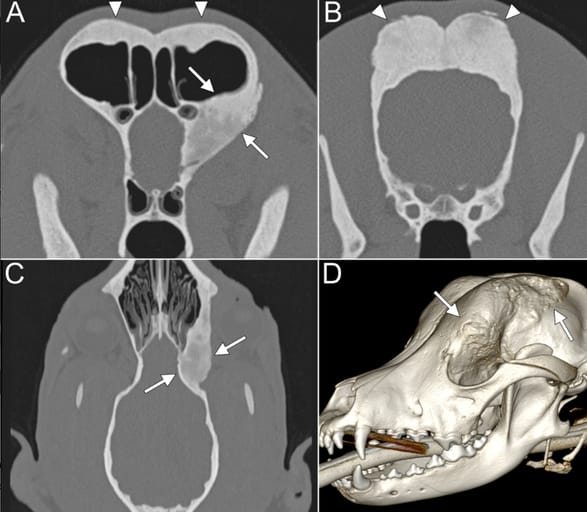

Imaging findings. (A) Transverse CT image showing marked thickening of the orbital lamina of the left frontal bone with smoothly marginated bone proliferation and sclerosis (solid arrows), as well as moderate bilateral thickening of the squama frontalis (arrowheads). (B) Transverse CT image showing marked bilateral thickening of the parietal bone with smoothly marginated bone proliferation and sclerosis (arrowheads). (C) Dorsal CT image showing marked thickening of the orbital lamina of the left frontal bone with smoothly marginated bone proliferation and sclerosis (solid arrows). (D) 3D volume-rendered image illustrating the extent of left frontal bone thickening and bone proliferation (solid arrows).

Case 1 presented with lateral exophthalmos of the left eye, with CT revealing thickened and sclerotic frontal, parietal, temporal, and occipital bones, extending into the orbit. Case 2 exhibited chronic serous lacrimal discharge due to nasolacrimal duct narrowing from hyperostotic changes in the right lacrimal and maxillary bones. Histopathology in case 1 indicated active bone remodeling, while case 2 displayed trabecular lamellar bone without neoplastic or infectious features. CHS was diagnosed in both cases. The exophthalmos in case 1 partially regressed over six months, while epiphora in case 2 persisted without progression.